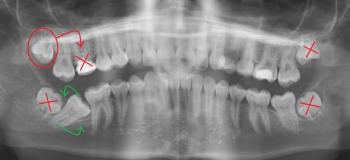

Clinical Exam & Diagnosis: The dentist will use transillumination (shining a light through the tooth) and magnification to determine the depth and extent of the crack.

-

Radiographs (X-rays): An X-ray is taken to rule out a fracture extending into the root or involvement of the nerve/pulp chamber.